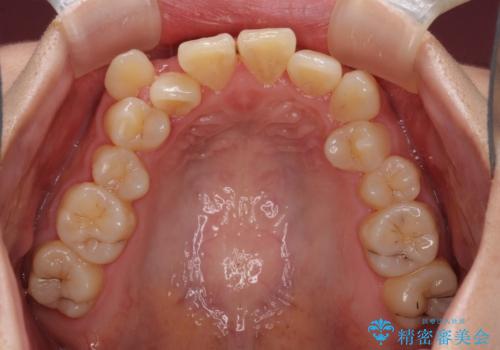

- 八重歯と叢生を気にして来院された患者様です。

上下の前歯が非接触であり、叢生や八重歯が顕著であったため、上顎左右第一小臼歯2本を抜歯して排列することとしました。

抜歯により移動量が多くなるため、ワイヤーや補助装置を活用し、その後インビザラインによる矯正治療を行うこととしました。